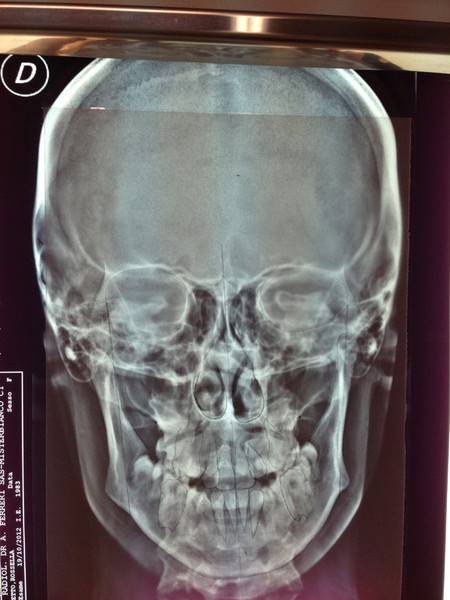

Paziente candidato a intervento di chirurgia Ortognatica